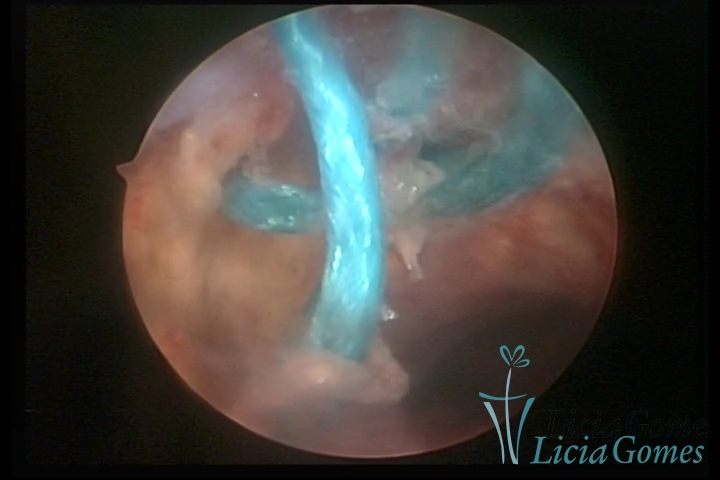

Cavidade com o Mirena®, sendo retirado sob visão direta